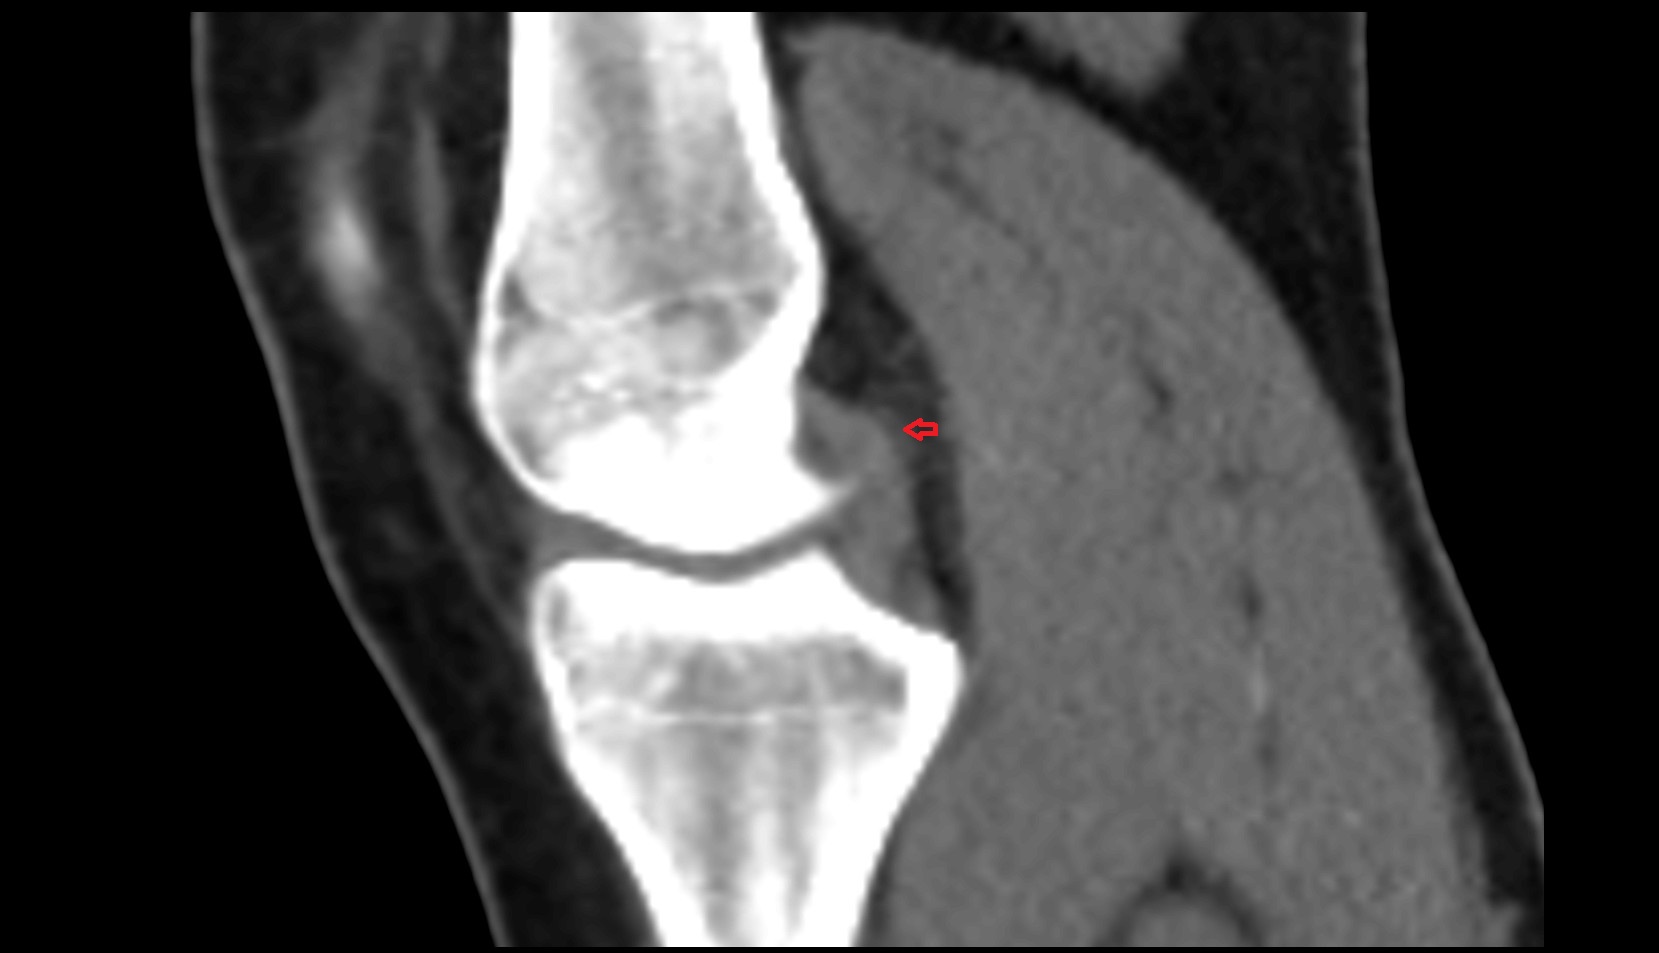

- Anterior cruciate ligament

- Posterior cruciate ligament

- Knee Joint